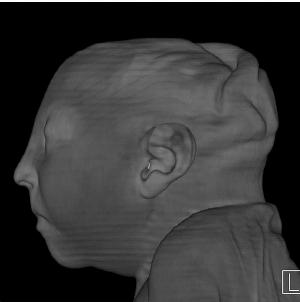

Figure 6. Images obtained in the case of a 24-year-old woman pregnant with twins, with characteristic rash at 9 weeks of pregnancy and confirmed Zika virus infection. (For each pair of images, the first image is of twin A, and the second image is of twin B.) At 14 weeks of gestational age, the fetal head size of both twins was normal. The head size never went below the 3rd percentile for either fetus in examinations at 19–28 weeks. (a, b) Sagittal and (c, d) axial fetal MR images were obtained at 36 weeks. (e, f) Axial and (g, h) surface reconstruction postnatal CT images and (i, j) axial T2-weighted and (k, l) coronal MR images were obtained 1 week after delivery at 38 weeks of gestational age. There is severe microcephaly with profound frontal lobe hypoplasia. Calcifications in the subcortical white matter at the gray matter–white matter junction are visualized. Both twins have a flattened appearance of the pons. The spinal cord is atrophic (best seen on a). Redundant skin is seen in the occipital region. There is polymicrogyria involving the frontal and parietal regions and atrophic cortex and white matter in the occipital regions. Each twin has hypoplasia of the corpus callosum, with prominent fornices. There is abnormal myelination in the occipital region that, in twin A (i), has the appearance of a cyst or septation within the ventricle. The cerebellum is somewhat small and nodular. There is lack of rotation of the hippocampi.